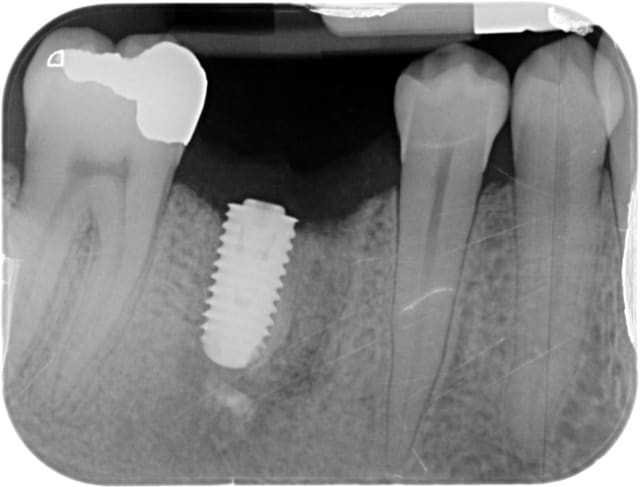

Voilà, c'est horrible mais ça arrive... Patient fumeur (10/15 cigarettes/jour avouées)

Janvier/février 2014 : découverte fortuite de la lésion apicale, j'ai voulu nettoyer avec de l'hydroxyde de calcium (il y avait aussi une perforation du plancher), le patient s'en est tiré avec une belle cellulite, et il en reste un peu dans l'os....

Extraction en avril, cicatrisation difficile au niveau muqueux, j'ai du mal expliquer qu'il faut retirer la prothèse partielle pour se brosser les dents.

Septembre : je pose l'implant, tout se passe bien, serré à 50, j'aurais pu l'enfouir davantage.

Janvier 2015 : oh la mauvaise surprise : une image en cupule en mésial, et une image angulaire en distal. De plus la gencive était légèrement percolée, on voyait la tête de vis de couverture.

je ne suis pas spécialiste des Axiom Anthogyr, mais c'est un implant à poser en principe en sous crestal...

là tu l'as posé juxta voir supracrestal...

il me semble avoir lu sur nonol que certains utilisateurs de l'axiom avaient quelques problèmes de cratérisation de leurs implant s'ils ne les enfouissaient pas assez, ce qui semble être aussi ton cas ici...

Change d'implant, des grosses spires jusqu'en haut c'est emmerdant.

C'est pire que ça, il y a une spire non synchronisée avec le reste au niveau du col pour augmenter les contraintes à ce niveau ;)

Par contre, les Axiom Anthogyr, doivent être posés en sous crestal de 1mm au moins, sans échauffement au forage bien sur.

L'implant est un 4x10mm